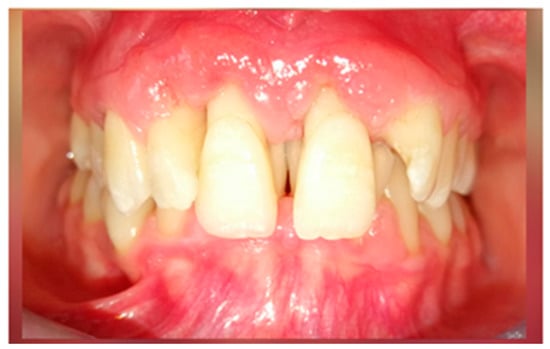

After 3 months of phase 1 of periodontal treatment, the patient returned to the clinic for supportive periodontal therapy (Figure 5). The clinically measured gingiva recession was about 6 mm for the maxillary central incisors and 4 mm for the lateral incisors. According to the Miller classification—class III gingival recession—vestibular marginal tissue recession extends to the mucogingival junction. Loss of interdental bone is apical to the CEJ but coronal to the apical extent of the vestibular marginal tissue recession (Figure 5).

The mobility of the teeth (Miller classification) was maintained at Class 2 for the two maxillary central incisors. This mobility was a result of inflammatory edema but also of the high degree of alveolar bone loss (Figure 6). The patient had no discomfort or pain.

Figure 6.

Clinical aspect after 3 months of periodontal therapy.